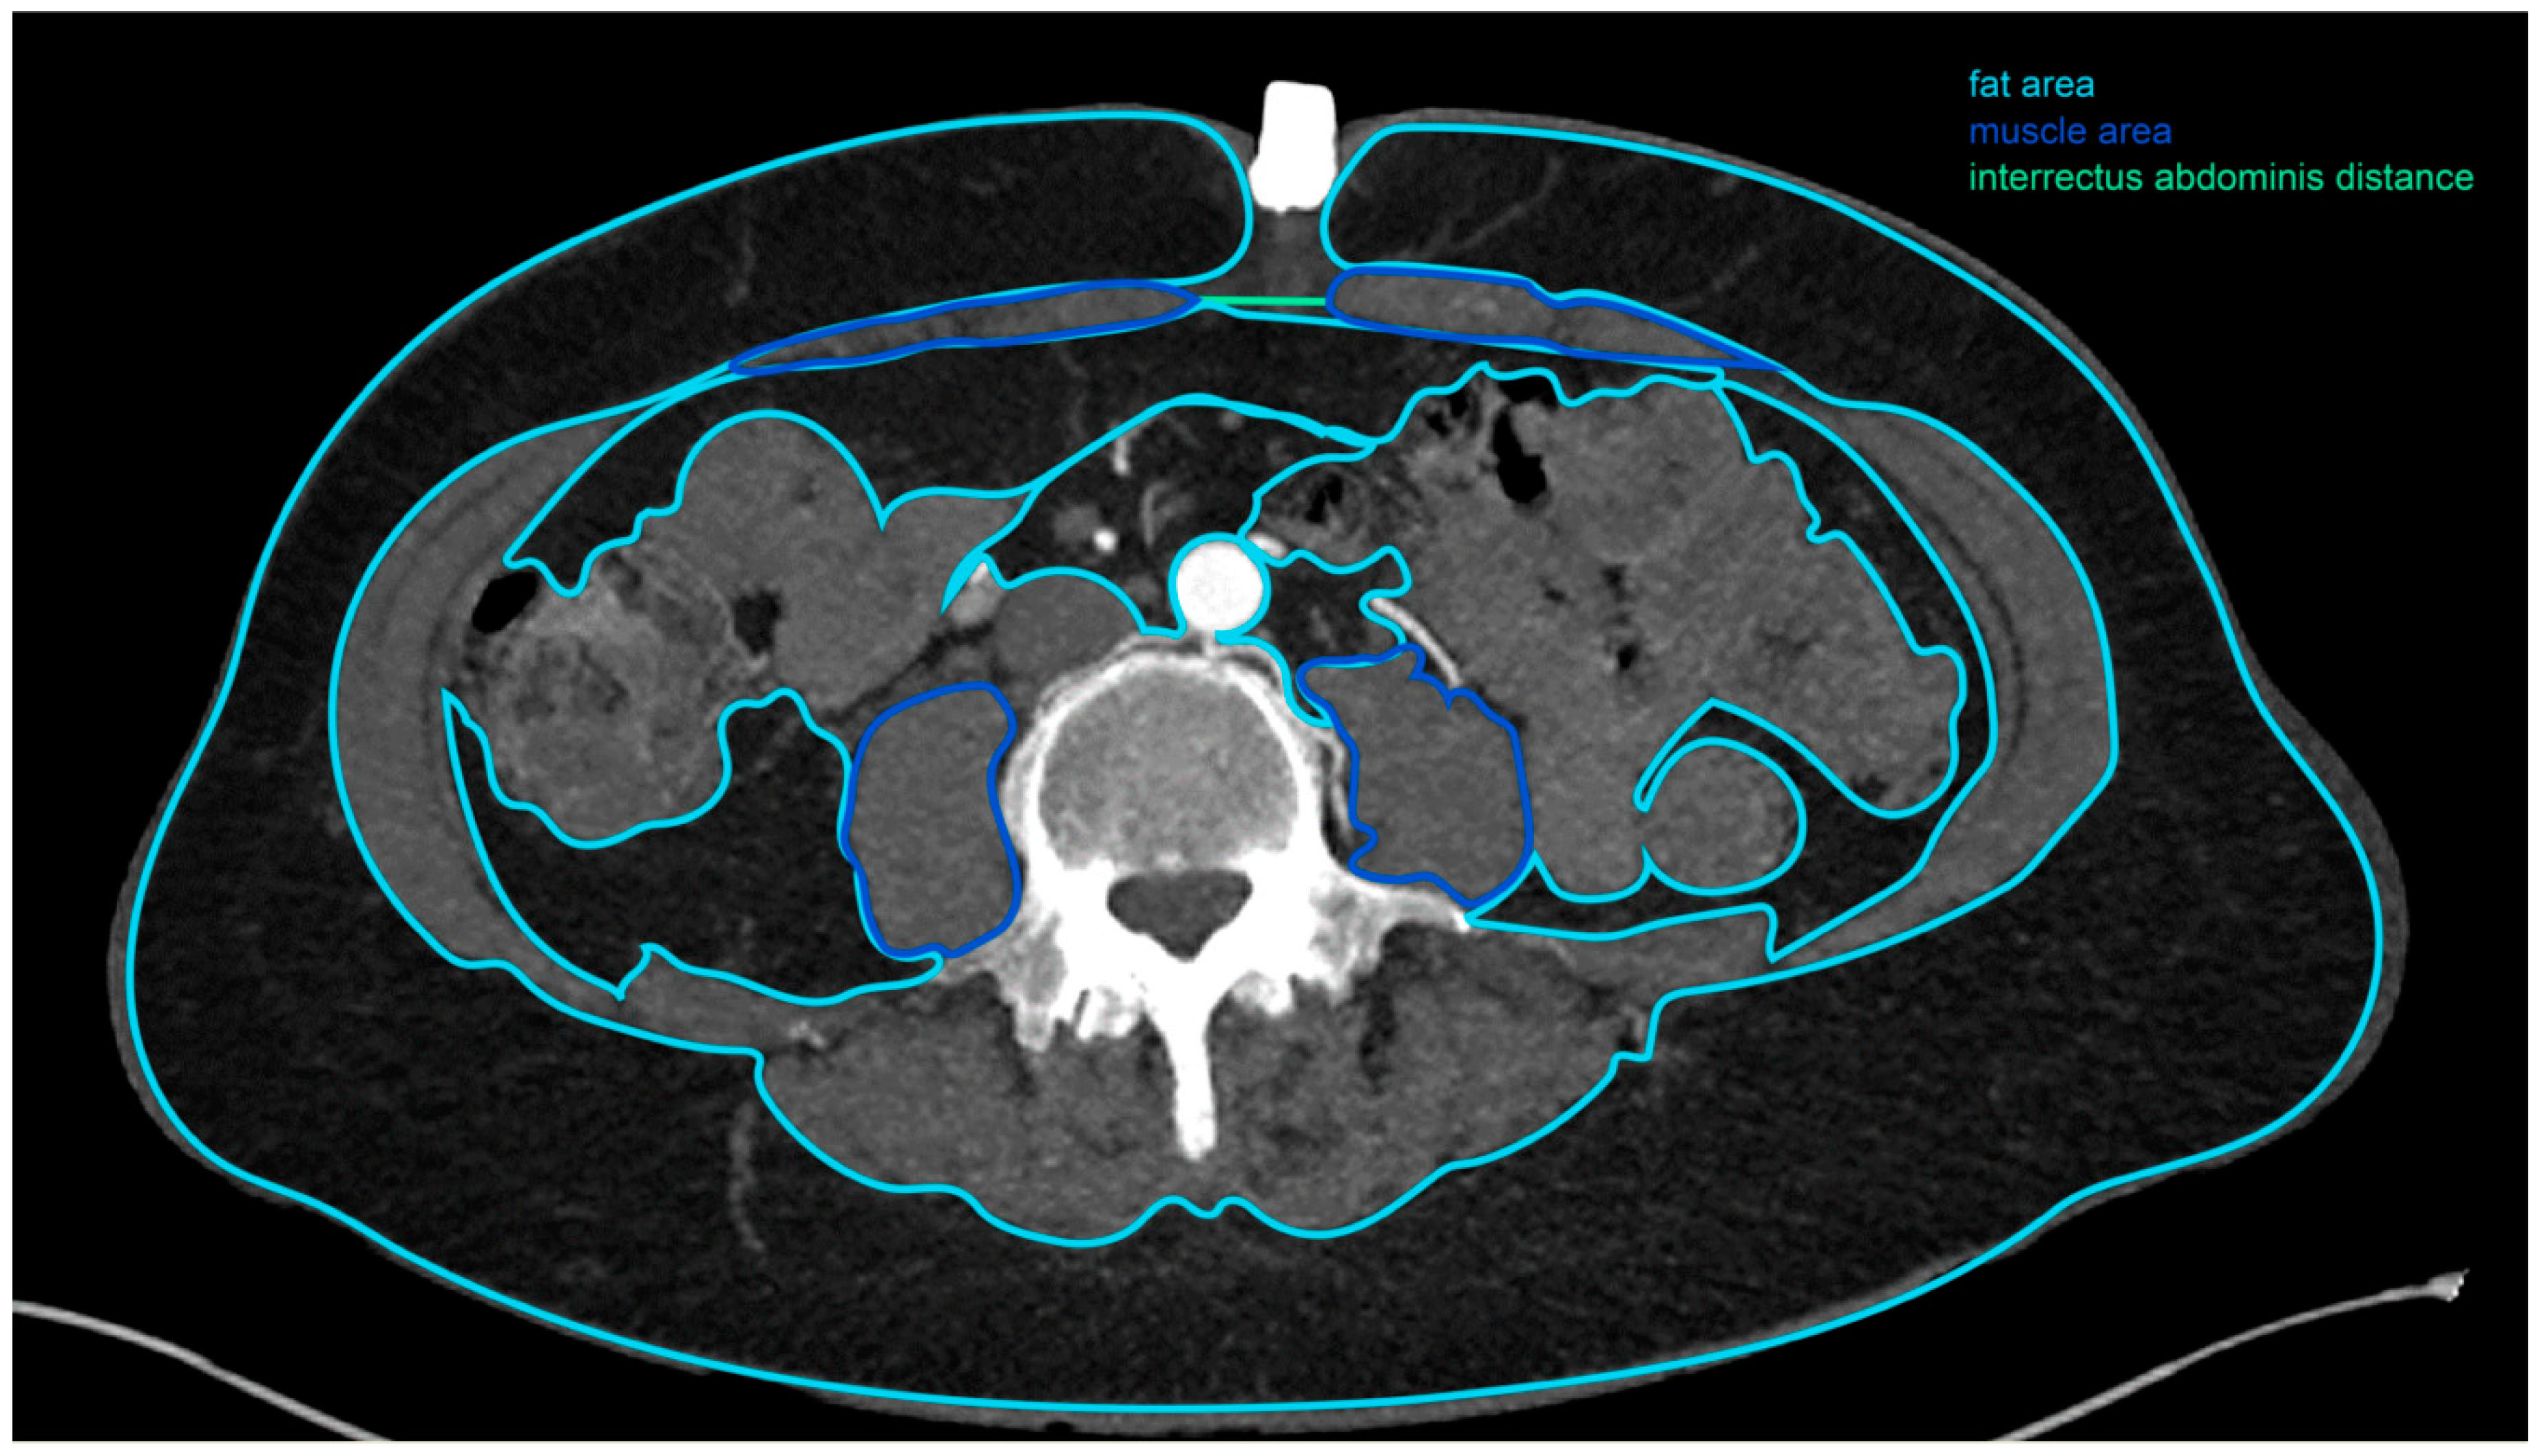

2.2. Computed Tomographic Angiogram Measurements